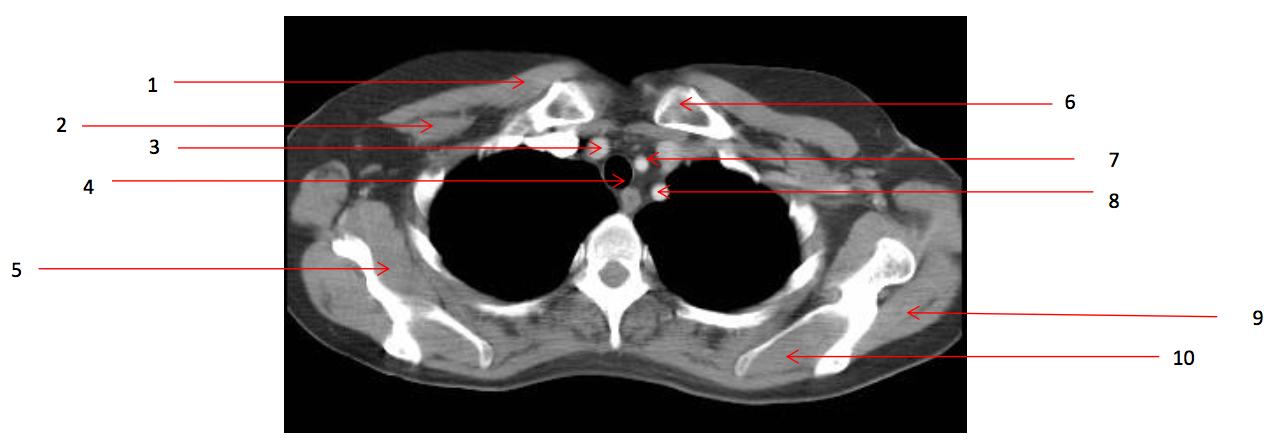

1

Number 2?

A

Rt pectoralis minor muscle

2

Number 6?

Lt clavicle

3

Number 10?

Lt supraspinatus muscle

4

Number 1?

Rt pectoralis major muscle

5

Number 8?

Lt subclavian artery

6

Number 4?

Trachea

7

Number 7?

Lt common carotid artery

8

Number 19?

Arch of aorta

9

Number 5?

Rt subscapularis muscle

10

Number 13?

Rt erectae spinae muscle

11

Number 9?

Lt infraspinatus muscle